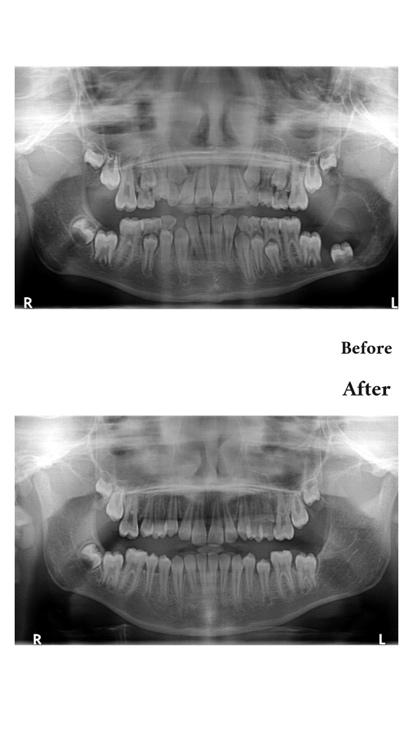

Case Study | Tumour and Cyst